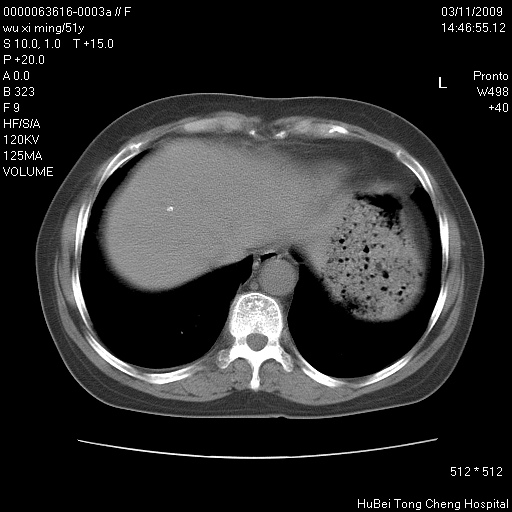

患者 女,51岁。因“胆囊炎,胆囊结石”,行常规术前胸部x线检查发现:右上肺结节病灶,建议行进一步检查。患者无咳嗽、咳痰及咯血等呼吸道症状,近期出现背部疼痛不适。

胸部ct轴位平扫(层厚10mm,螺距1.5,重建间隔10mm;部分层面:层厚3mm,螺距1.0,重建间隔3mm),图像如下:

右肺周围型肺癌伴肺内转移及胸椎转移。已无手术机会。